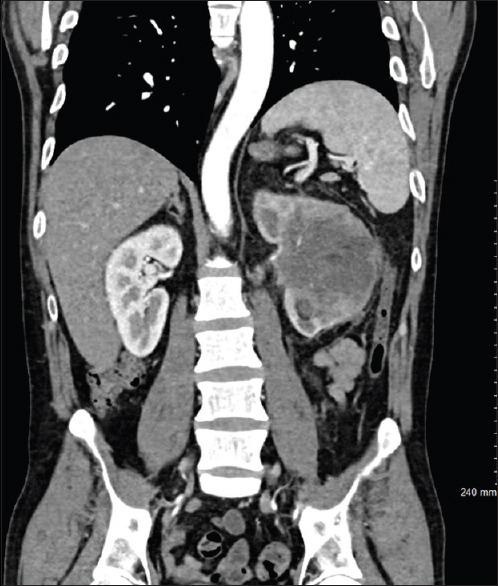

Right ventricular (RV) metastasis from an upper tract urothelial carcinoma without inferior vena cava or right atrial involvement is an extremely rare event which highlights the heterogeneity of this disease process. We report a case of a 43-year-old man presenting for long-standing hematuria and left flank pain. Computed tomography revealed a left renal mass with para-aortic lymphadenopathy, in addition to a potential mass in the RV. The mass involving the RV was confirmed on subsequent cardiac evaluation with magnetic resonance imaging (MRI) and echocardiography. After discussion in a multidisciplinary tumor board, the patient underwent a left nephrectomy, regional lymphadenectomy, and excision of metastatic RV tumor with bovine patch reconstruction. Final pathology reported invasive urothelial carcinoma in the left kidney with involvement of regional para-aortic lymph nodes and metastatic tumor in the RV (T4N3M1, AJCC 8 edition). The patient did well postoperatively and completed adjuvant Cisplatin-Gemcitabine systemic chemotherapy. This is an important addition to the literature as it highlights the aggressive and heterogeneous nature of urothelial carcinoma and the utility of cardiac MRI in surgical planning.

https://cdn.ncbi.nlm.nih.gov/pmc/blobs/cfd2/8815341/ec047b6facbe/UA-14-89-g001.jpg